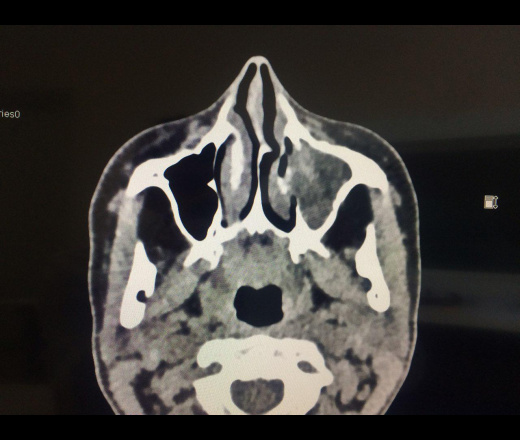

Ж, 41 год, боли в области лица слева. Коллеги это инородное тело это пломбировочный материал? это же гайморит с деструкцией стенки а не объем? Подскажите пож как правильно в данном случае описать изменения и  сформировать заключение?

Да, это   инородное тело, скорее всего, пломбировочный материал, плюс мицетомы; но,  как правильно отметил И.Бондаренко, для  правильного описания и заключения нужны дайкомы.